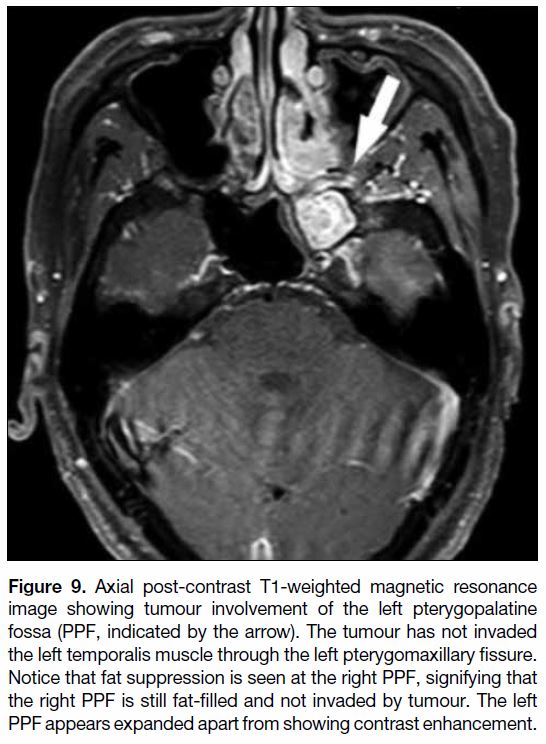

pterygopalatine fossa is commonly denoted as T3 and

is cross-roads in head and neck imaging (Figure 9).

Figure 9. Axial post-contrast T1-weighted magnetic resonance

image showing tumour involvement of the left pterygopalatine

fossa (PPF, indicated by the arrow). The tumour has not invaded

the left temporalis muscle through the left pterygomaxillary fissure.

Notice that fat suppression is seen at the right PPF, signifying that

the right PPF is still fat-filled and not invaded by tumour. The left

PPF appears expanded apart from showing contrast enhancement.

Anteriorly it continues into the orbit through the inferior

orbital fissure (Figure 10). Posteriorly and superiorly, it

communicates with the cavernous sinuses of the middle

cranial fossa through the foramen rotundum (Figure 10).